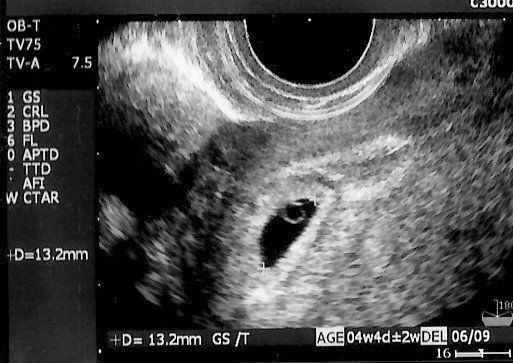

妊娠5週目のエコー写真 ようやく妊娠成立!

不妊治療専門クリニックで5回目の体外受精を行い、その後医師から妊娠していることを告げられました。妊娠5週目の画像です。当時は、妊娠したうれしさより、正直なところ「これでもうあの治療のつらさから解放されるかもしれない」という気持ちの方が強かったです。まだ流産の可能性が高いということで、夫も私も心から喜ぶことはできませんでした。